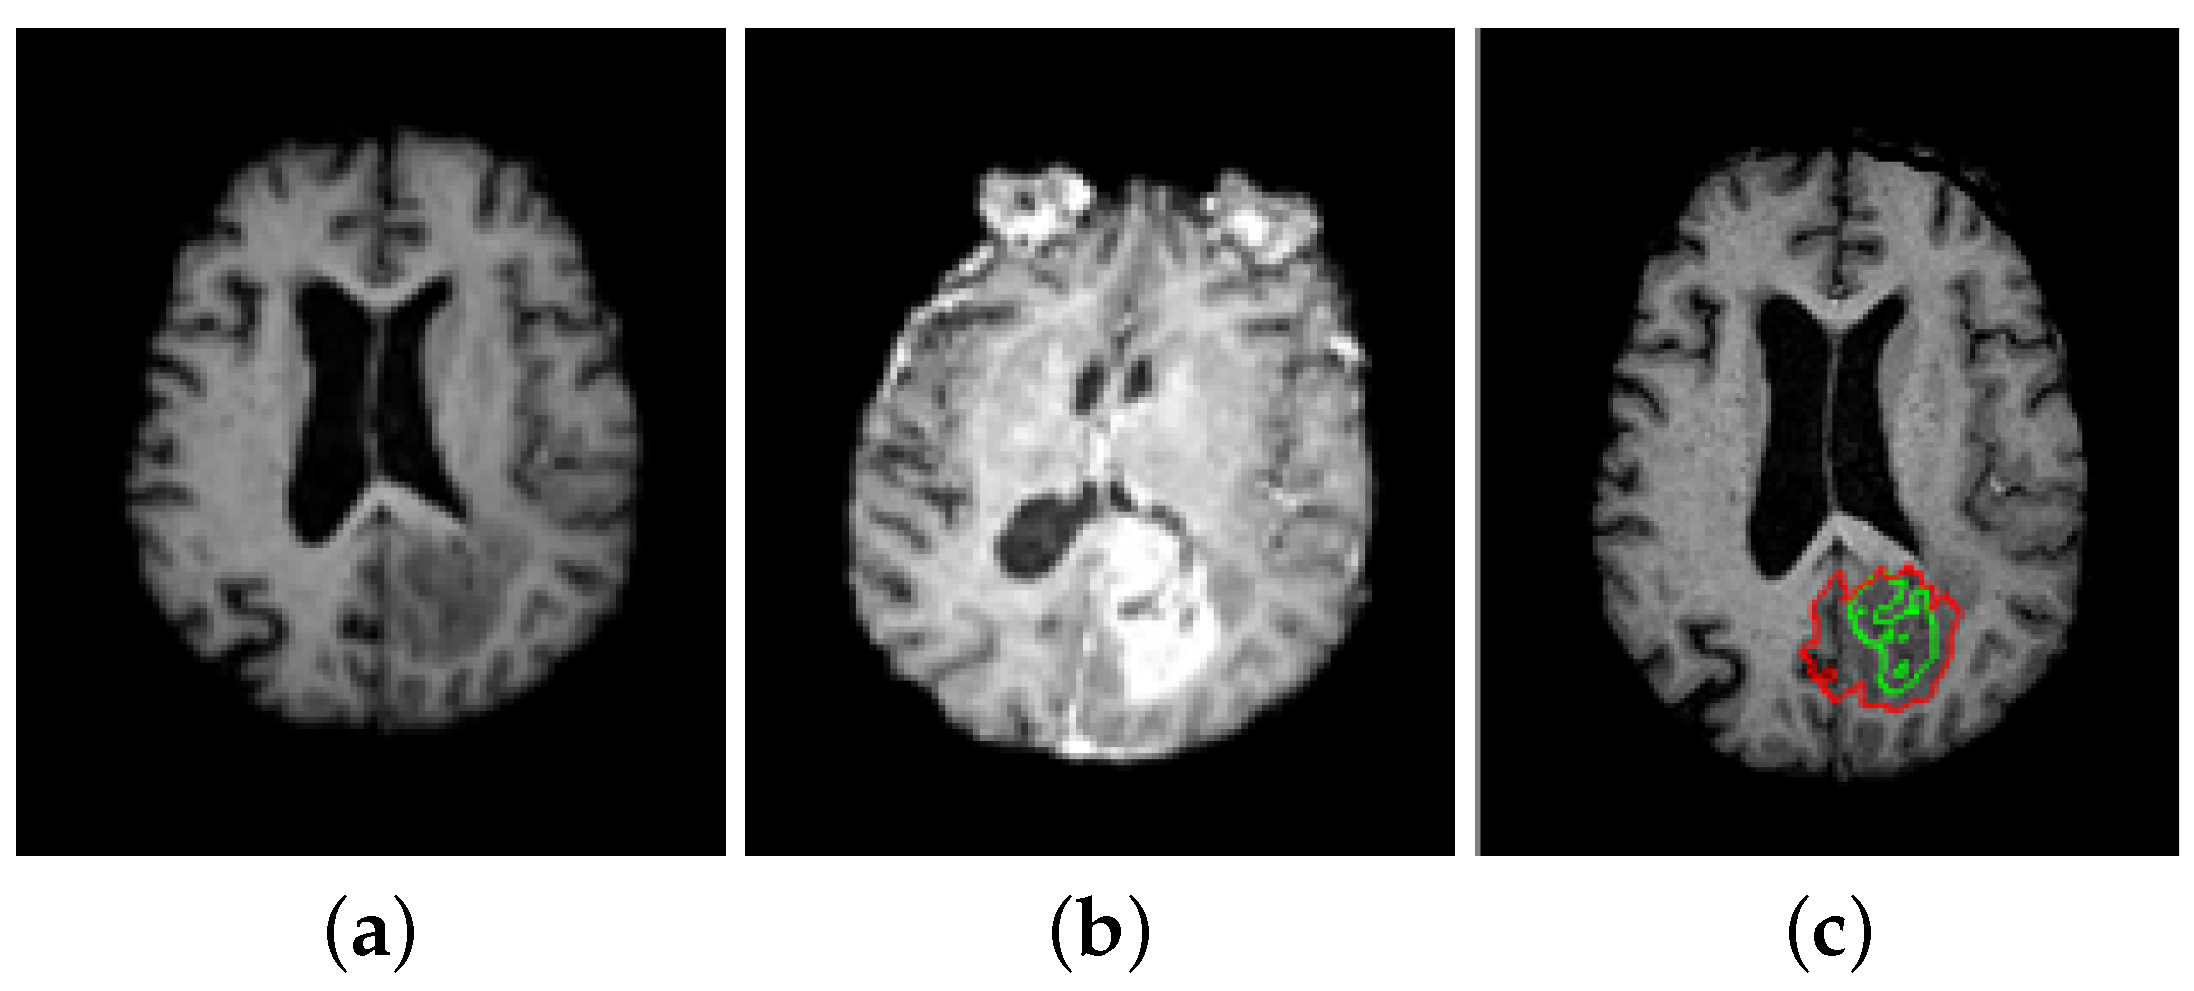

5. A Unified Framework for Brain Tumor Segmentation

- Bourouis, S.; Hamrouni, K. 3D segmentation of MRI brain using level set and unsupervised classification. Int. J. Image Graph. (IJIG) 2010, 10, 135–154. [Google Scholar] [CrossRef]